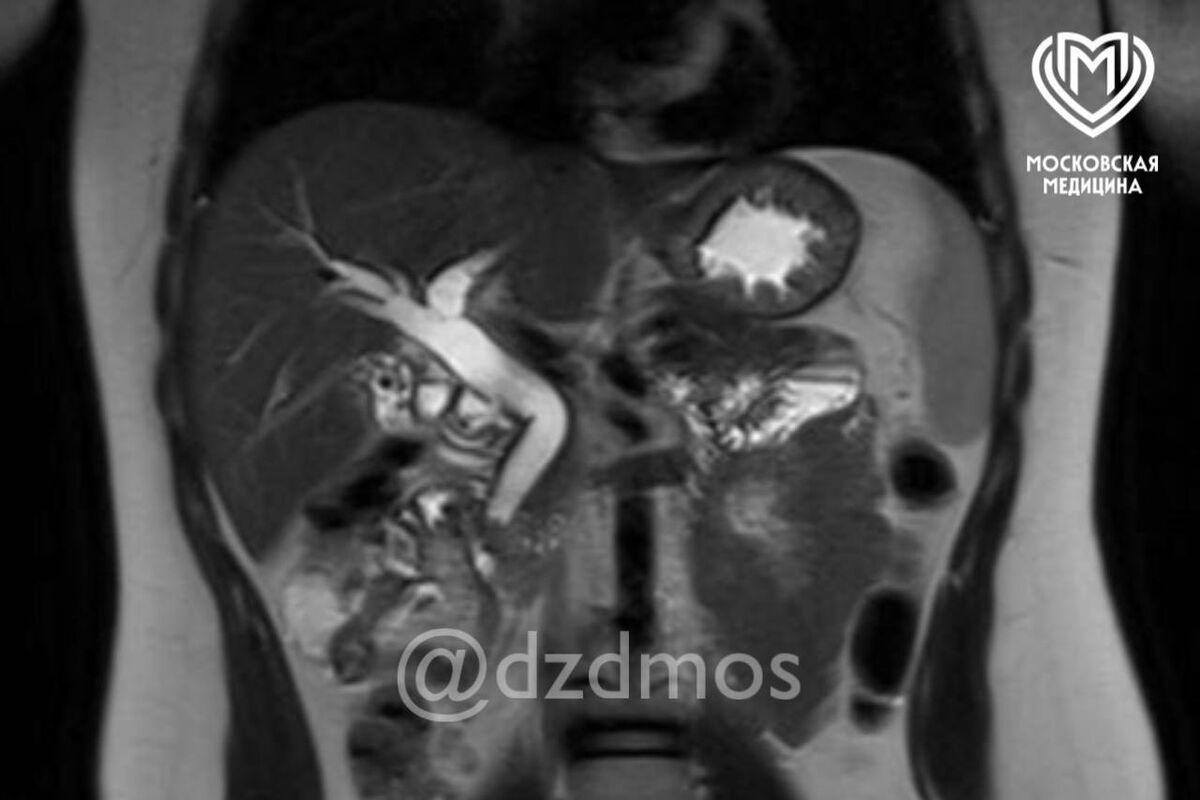

Ребенок поступил в медицинское учреждение с болями в животе, рвотой и общей слабостью. Обследование показало, что в желчном пузыре ребенка скопилось огромное количество камней диаметром до 3 мм. Один из них перекрыл общий желчный проток, что угрожало жизни девочки.

Медики пояснили, что застрявшие в общем желчном протоке камни вызывают нарушение оттока желчи из печени — это приводит к развитию желтухи, начинает страдать печень, как и в случае с юной пациенткой. В тяжелых формах, как отметили специалисты, может развиться воспаление поджелудочной железы.

«Ребенку сделали эндоскопическую папиллосфинктеротомию: специальным аппаратом рассекли сосочек, впадающий в желчный проток, расширили его мышечное кольцо и извлекли камень. Вторым этапом удалили желчный пузырь, полностью забитый камнями», — рассказали в пресс-службе депздрава.